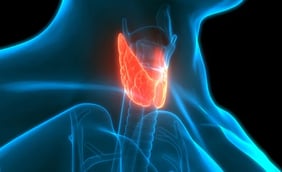

What Are Thyroid Nodules?

Thyroid nodules are solid or fluid-filled lumps or bumps. They're found on your thyroid, a small gland in your neck. This gland makes thyroid hormone, which affects your metabolism (the internal process that turns your food into energy), heart rate, and many other systems in your body. Sometimes, cells in your thyroid can grow out of control and form a lump, called a thyroid nodule.